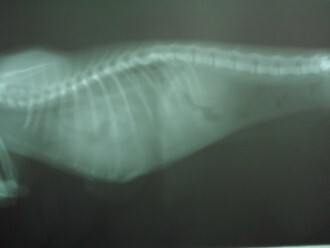

主題: 橫隔破裂 造成呼吸異常的貓 修捕橫隔 申請者姓名: 劉雅雲 花色: 申請日期: 2012-04-29 10:58:35 申請者部落格: 申請者臉書網址: 所在縣市/合作醫院: 高雄市/樂生動物醫院 治療費用: 4400元 需求人數: 5人 已結案 (2013-06-27 13:18:45) 報名人員: ShowRong Lin(已付款)、Ku-ai Gina Chen(已付款)、蕭泰咪(已付款)、Paula Wu(已付款)、Elsa Tu(已付款)、 候補人員: julie lee、小舟、 動物病情說明: 這是在高雄建國路的享溫馨KTV停車場的貓咪,因為她不知為何一直叫, 觀察後呼吸有點怪怪的, 也不吃, 醫生一看貓也覺得貓的呼吸有問題, 先輕微鎮定後做血檢 和照X光.

發現貓的橫隔破一個洞, 有可能是車撞到造成, 有些腹部的器官跑到胸腔, 肺只有一邊有作用, 消化系統也有影響, 所以不理她的話會慢慢死亡, 因為橫格修補須麻醉對這隻瘦弱的貓咪有危險, 而且貓的橫隔破裂已經不知多久, 但不修補她會沒命, 所以經過一番評估, 醫生進行手術搶救希望可以修補成功,貓咪最後沒撐過. 已經當天使去了..

X光2片 400*2=800